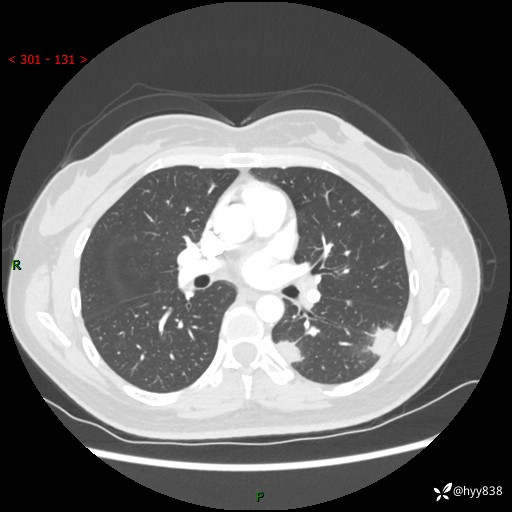

36岁/女,左侧下胸部阵发性疼痛2周,乏力1周。精彩无限,等你来诊---结果公布~

【患者信息】:36岁/女

【主诉】:左侧下胸部阵发性疼痛2周,乏力1周

【现病史及既往史】:患者自诉2周前饮酒后出现左侧下胸部阵发性疼痛,不随呼吸改变,无咳嗽咳痰、头晕头痛、咳血、呼吸困难等不适,于当地第一人民医院查胸部CT提示肺部感染,随后前往我院门诊给予抗感染(左氧氟沙星)治疗1周,自诉胸痛较前好转,感乏力、头晕,偶尔干咳,无咳痰,无发热、畏寒、胸闷、咯血、四肢酸痛、腹泻、腹痛等不适,门诊复查胸部CT提示:左肺下叶感染,病灶较前增加增大,遂以“肺部感染”收入我科。 起病以来,患者精神、饮食、睡眠可,大小便正常,体力体重无明显变化。

【检查】:胸部CT增强(外院平扫)